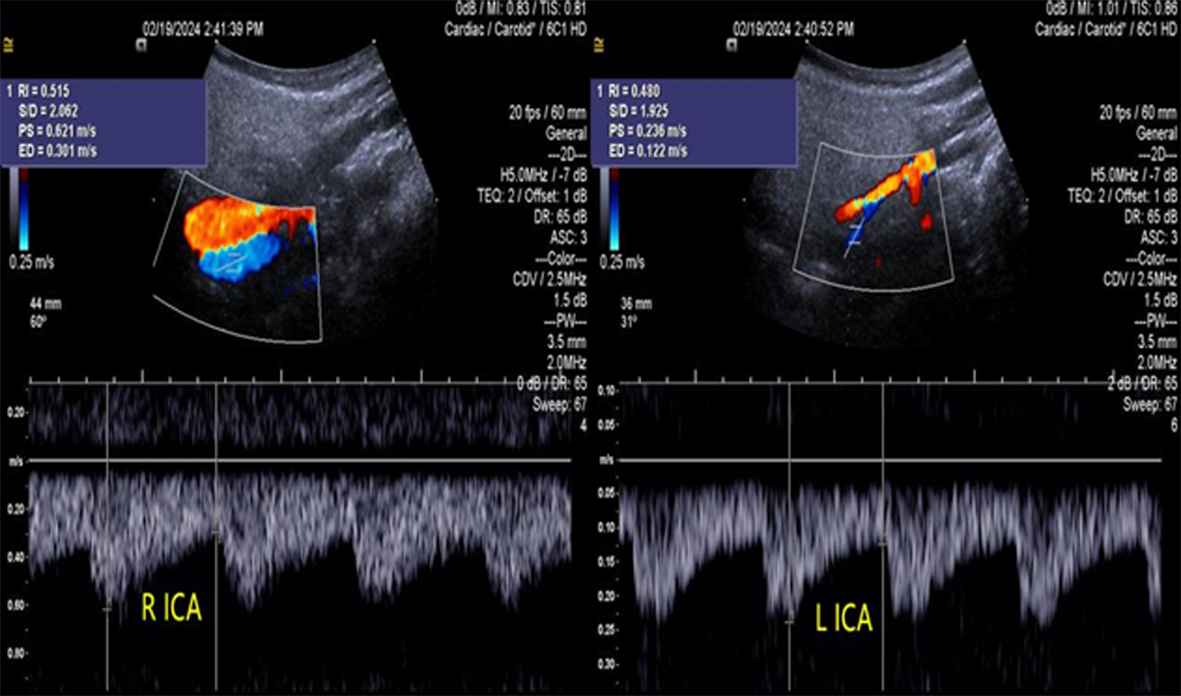

Objective To summarize diagnostic and differentialdiagnostic approaches for initial detection of moyamoya disease (MMD) using carotid ultrasound (CAU). Methods We report two patients who were first diagnosed with MMD by CAU and summarize the diagnostic reasoning and differential considerations. Relevant literature was reviewed to contextualize these findings. Results Case 1: A 57-year-old female presented with a >10 year history of dizziness and headache with recurrence over 3 days. CAU showed a reduced diameter of the left internal carotid artery (ICA), decreased flow velocity, and a lower resistance index, raising suspicion for severe intracranial stenosis or occlusion and prompting clinical exclusion of MMD. Magnetic resonance angiography (MRA) confirmed severe stenosis of the left ICA with absent distal branches and multiple small abnormal vascular networks in the left suprasellar region, consistent with MMD. Case 2: A 23-year-old male presented with dizziness for >1 year and transient right upperlimb weakness for 1 day. CAU and transcranial color Doppler (TCCD) showed a narrowed right ICA with reduced flow velocity and increased resistance index, suggesting chronic occlusion of the right middle cerebral artery and stenosis of the left middle cerebral artery, raising the possibility of MMD. MRA demonstrated an indistinct right ICA and right middle cerebral artery and narrowing of the left middle cerebral artery. On followup, the patient was diagnosed with MMD. Conclusion When CAU reveals a small internal carotid artery diameter accompanied by slowed flow velocity, clinicians should perform a comprehensive evaluation-including TCCD and further vascular imaging-to avoid missed or incorrect diagnoses of MMD.